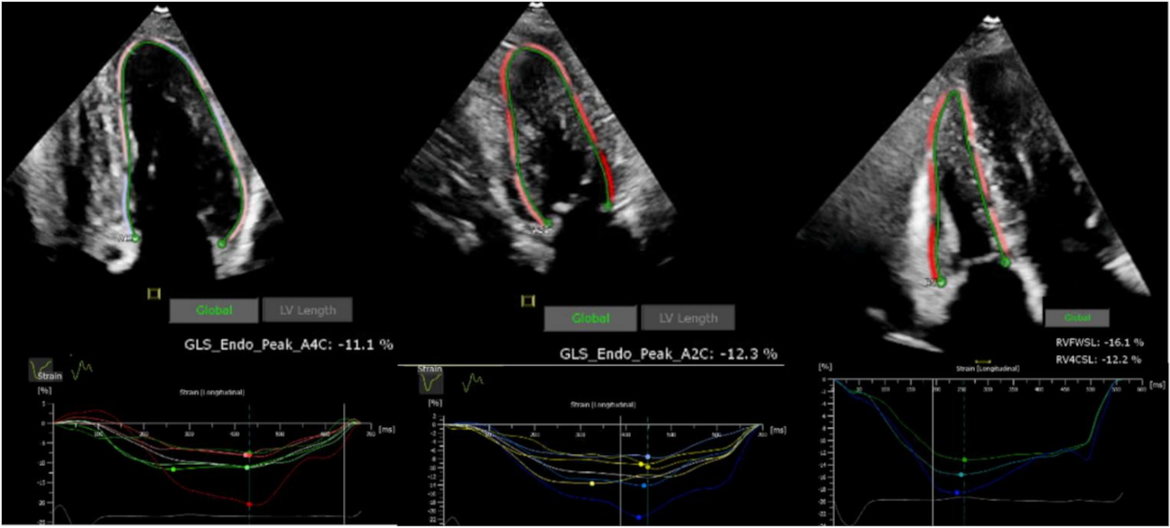

5.1. Transthoracic Echocardiography

- Advanced parameters, including GLS and MW, may independently predict risk of MACE in FD, consistent with data from other non-ischaemic cardiomyopathies but further work is required;